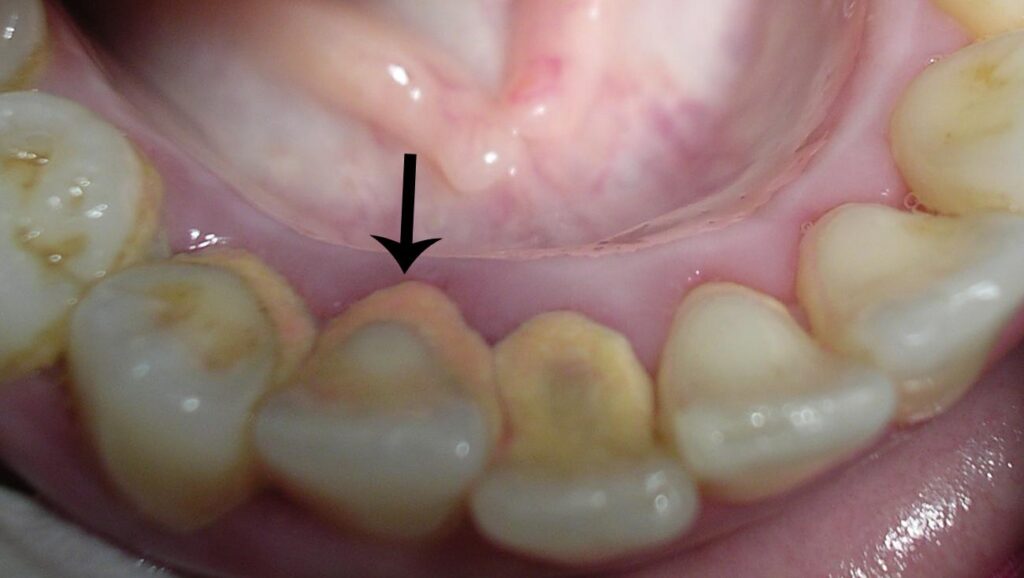

Calculus, also known as tartar, is a yellow, tan, brown, or white deposit of minerals found on the tooth’s surface. It’s formed from pre-existing hardened plaques. The formation of calculus differs in individuals. This condition is dependent on the pH of your saliva and the quantity of calcium and other substances present in your saliva. If not treated, calculus forms a bridge taking over multiple teeth, spaces between them, and the gums.

Calculus bridge is commonly found on the upper molars and lower anterior teeth due to their proximity to the ducts of the salivary gland.